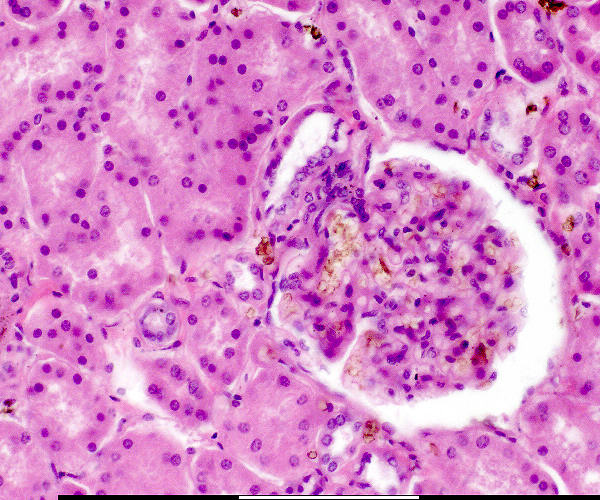

Makula densa / Macula densa Pariëtale selle / Parietal cells Pariëtale laag / Parietal layer Podosiete / Podocytes Urinêre spasie / Urinary space Vaskulêre pool / Vascular pole Visserale laag / Visceral layer Urinêre pool / Urinary pole Jukstaglomerulêre apparaat / Juxtaglomerular apparatus